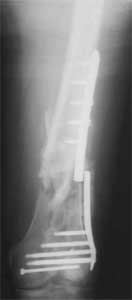

Attached are few examples from our Hospital:

B. Fixation loosening: distal cutting of the nail, non-unions do happen (cases attached).

Locking Plating has more distal screws than any nail, fixed angles and provides much better fixation, especially in osteoporotic bone.

A new toy is more interesting and fashionable. And anyway it is not panacea, i have already seen presentations with LISS failures like the attached one presented by D.Seligson. And people also demonstrated incisions say that the method is not so LESS invasive as it supposed to be.